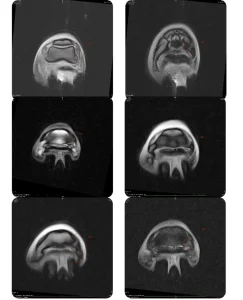

- Other advanced tests, such as scintigraphy and magnetic resonance imaging, in collaboration with specialised equine veterinary hospitals.